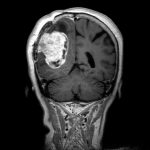

625

'25年4月

60代

円蓋部髄膜腫

頭蓋内腫瘍摘出術

No.’25_27 手術前1

No.’25_27 手術前2

No.’25_27 摘出 前

No.’25_27  摘出 中

No.’25_27 摘出 後